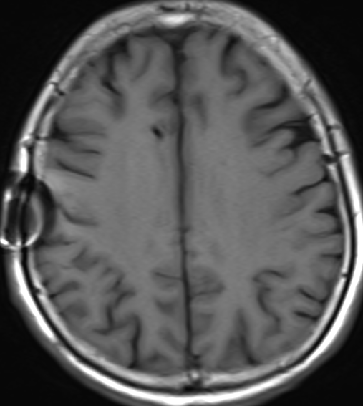

2013-8-2 CT

腰穿脑压240